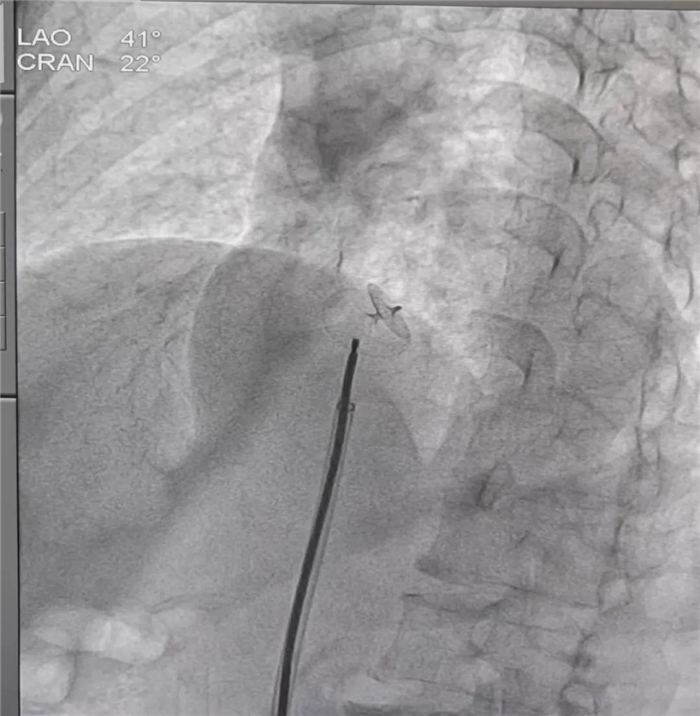

据悉,患者罗女士(化名)来自拉萨市,今年61岁,既往有反复头晕、心慌等不适症状,7月6日到我院心血管内科就诊。经右心造影检查明确患者为卵圆孔未闭,经心血管内科全科室研究讨论后,决定为该患者进行卵圆孔未闭介入封堵术。13日下午,在心内科主任朱永彪的指导下,我院心血管内科通力合作,用介入封堵术取代外科手术,通过一根导管,经右股静脉途径将封堵器沿输送鞘置入并成功封堵卵圆孔,术中多角度显示封堵器形态良好。

手术成功